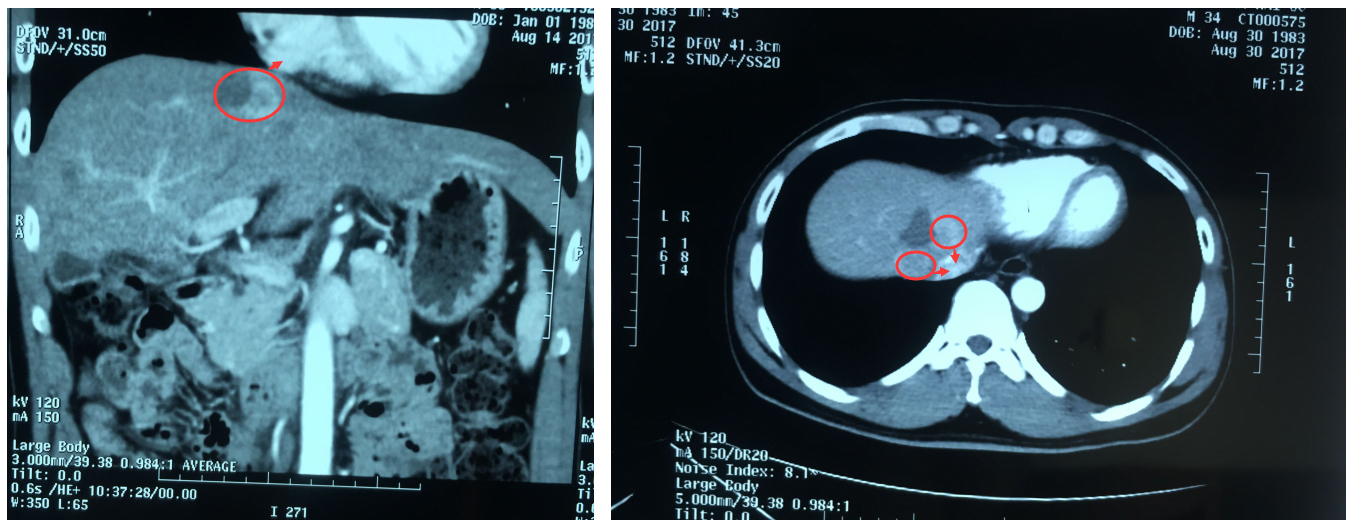

更讓人心痛的是,經(jīng)檢查,他的肝臟腫瘤位置非常特殊:不僅位于膈腳下腔靜脈旁,而且距離心臟只有1.5cm,不宜再行傳統(tǒng)外科手術(shù)。常規(guī)腫瘤消融術(shù)又不足以徹底消滅腫瘤,那該怎么辦呢?

▲患者肝臟腫瘤距離心臟1.5cm,位于膈腳下腔靜脈旁